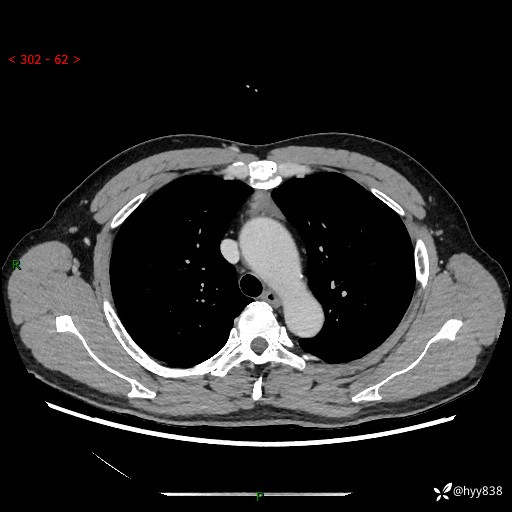

患者性别:女

患者年龄:49岁

简要病史:跟骨骨折,常规CT发现纵隔占位

增强(动脉期+静脉期)